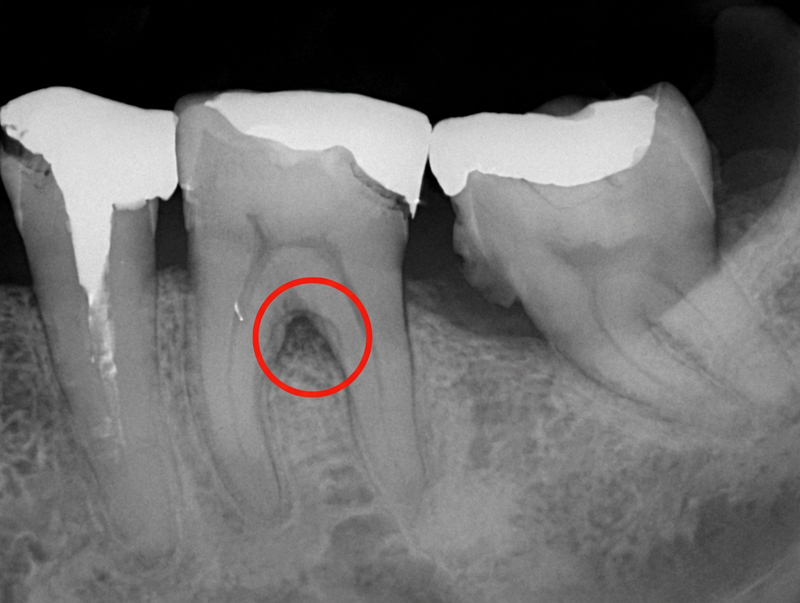

CT/レントゲン検査

歯周病は顎の骨を溶かしてしまう病気です。その進行状況を正確に把握するために、CT検査を行います。CTは3Dで立体的な画像を撮影できる装置で、歯周病の進行度を詳しく調べることができます。